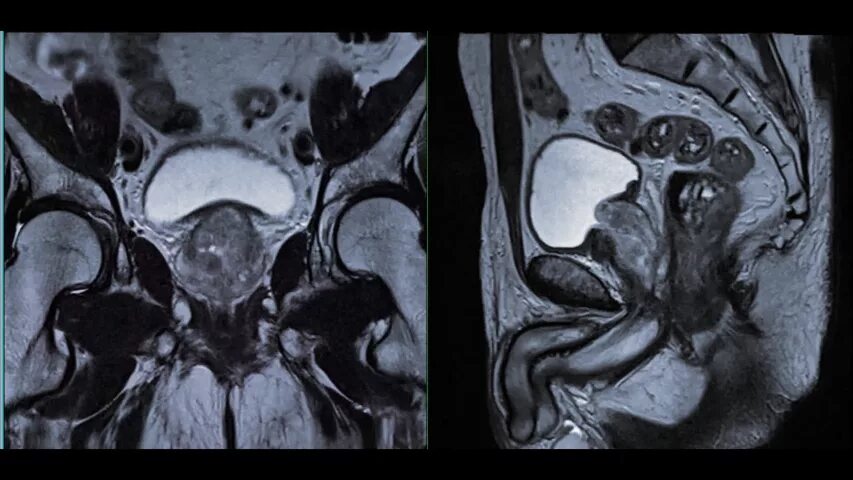

Перед мрт простаты